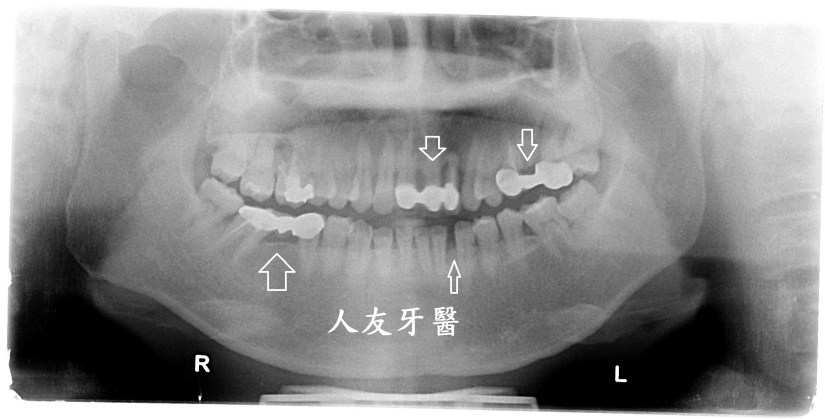

牙套, 牙橋, 矯正, 美白, 門牙, 全瓷牙矯正+植牙+搭配更換全鋯牙後美白(案例分享) 9 一月, 2020 naomi (術前照片)上門牙舊式牙橋及牙縫 患者經評估溝通後利用全口矯正關閉左下方的縫隙,上顎門牙牙橋及左上方加右下方牙橋在矯正前拆除,矯正期間有美容樹脂牙橋配戴,左上方第二小臼齒因齒質不佳建議後拔除植牙。矯正把縫隙關小後,裝上正式牙套及牙橋。 矯正期間裝上暫時牙套 拉出空間後植牙 患者在矯正及搭配全鋯牙套完成後也利用居家美白讓齒色達到滿意的效果。 分享此文: 分享到 X(在新視窗中開啟) X 分享到 Facebook(在新視窗中開啟) Facebook 喜歡 正在載入... 發表者:naomi 檢視 naomi 的所有文章